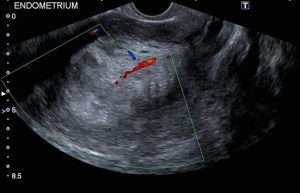

سونوگرافی (Ultrasound)

سونوگرافی اغلب یکی از اولین آزمایشاتی است که برای بررسی رحم، تخمدانها و لولههای فالوپ در زنان مبتلا به مشکلات احتمالی زنانه استفاده میشود. اولتراسوند از امواج صوتی برای گرفتن عکس از داخل بدن استفاده میکند. یک دستگاه کوچک (که مبدل – transducer – یا کاوشگر – probe – نامیده میشود) امواج صوتی را منتشر کرده و پژواکها را هنگام جهش از اندامها دریافت میکند. یک کامپیوتر پژواکها را به تصاویر تبدیل میکند.

برای سونوگرافی لگن، مبدل روی پوست قسمت تحتانی شکم (abdomen) حرکت میکند. اغلب، برای گرفتن عکسهای خوب از رحم، تخمدانها، لولههای فالوپ و مثانه باید پر باشند. به همین دلیل است که از زنانی که سونوگرافی لگن دریافت میکنند، خواسته میشود قبل از انجام آزمایش، آب زیادی بنوشند.

سونوگرافی ترانس واژینال (transvaginal ultrasound یا TVUS) اغلب برای بررسی رحم بهتر است. برای این آزمایش، پروب TVUS (که مانند مبدل اولتراسوند عمل میکند) داخل واژن قرار میگیرد. از تصاویر TVUS میتوان برای مشاهده اینکه آیا رحم حاوی توده (تومور) است یا اینکه آندومتر ضخیم تر از حد معمول است یا خیر، استفاده کرد که میتواند نشانه سرطان آندومتر باشد. همچنین این روش ممکن است به بررسی اینکه آیا سرطان در لایه عضلانی رحم (میومتر) رشد میکند یا خیر، کمک کند.

ممکن است قبل از سونوگرافی از یک لوله کوچک برای قرار دادن آب نمک (سالین یا saline) در رحم استفاده شود. این کار به پزشک کمک میکند تا پوشش رحم را با وضوح بیشتری ببیند. این روش سونوگرافی انفوزیون نمک (saline infusion sonogram) یا هیستروسونوگرافی (hysterosonogram) نامیده میشود. (Sonogram اصطلاح دیگری برای سونوگرافی است.)

سونوگرافی میتواند برای دیدن پولیپ (رشد) آندومتر، اندازه گیری ضخامت آندومتر به پزشکان کمک کند تا ناحیه ای را که میخواهند بیوپسی کنند، مشخص کنند.